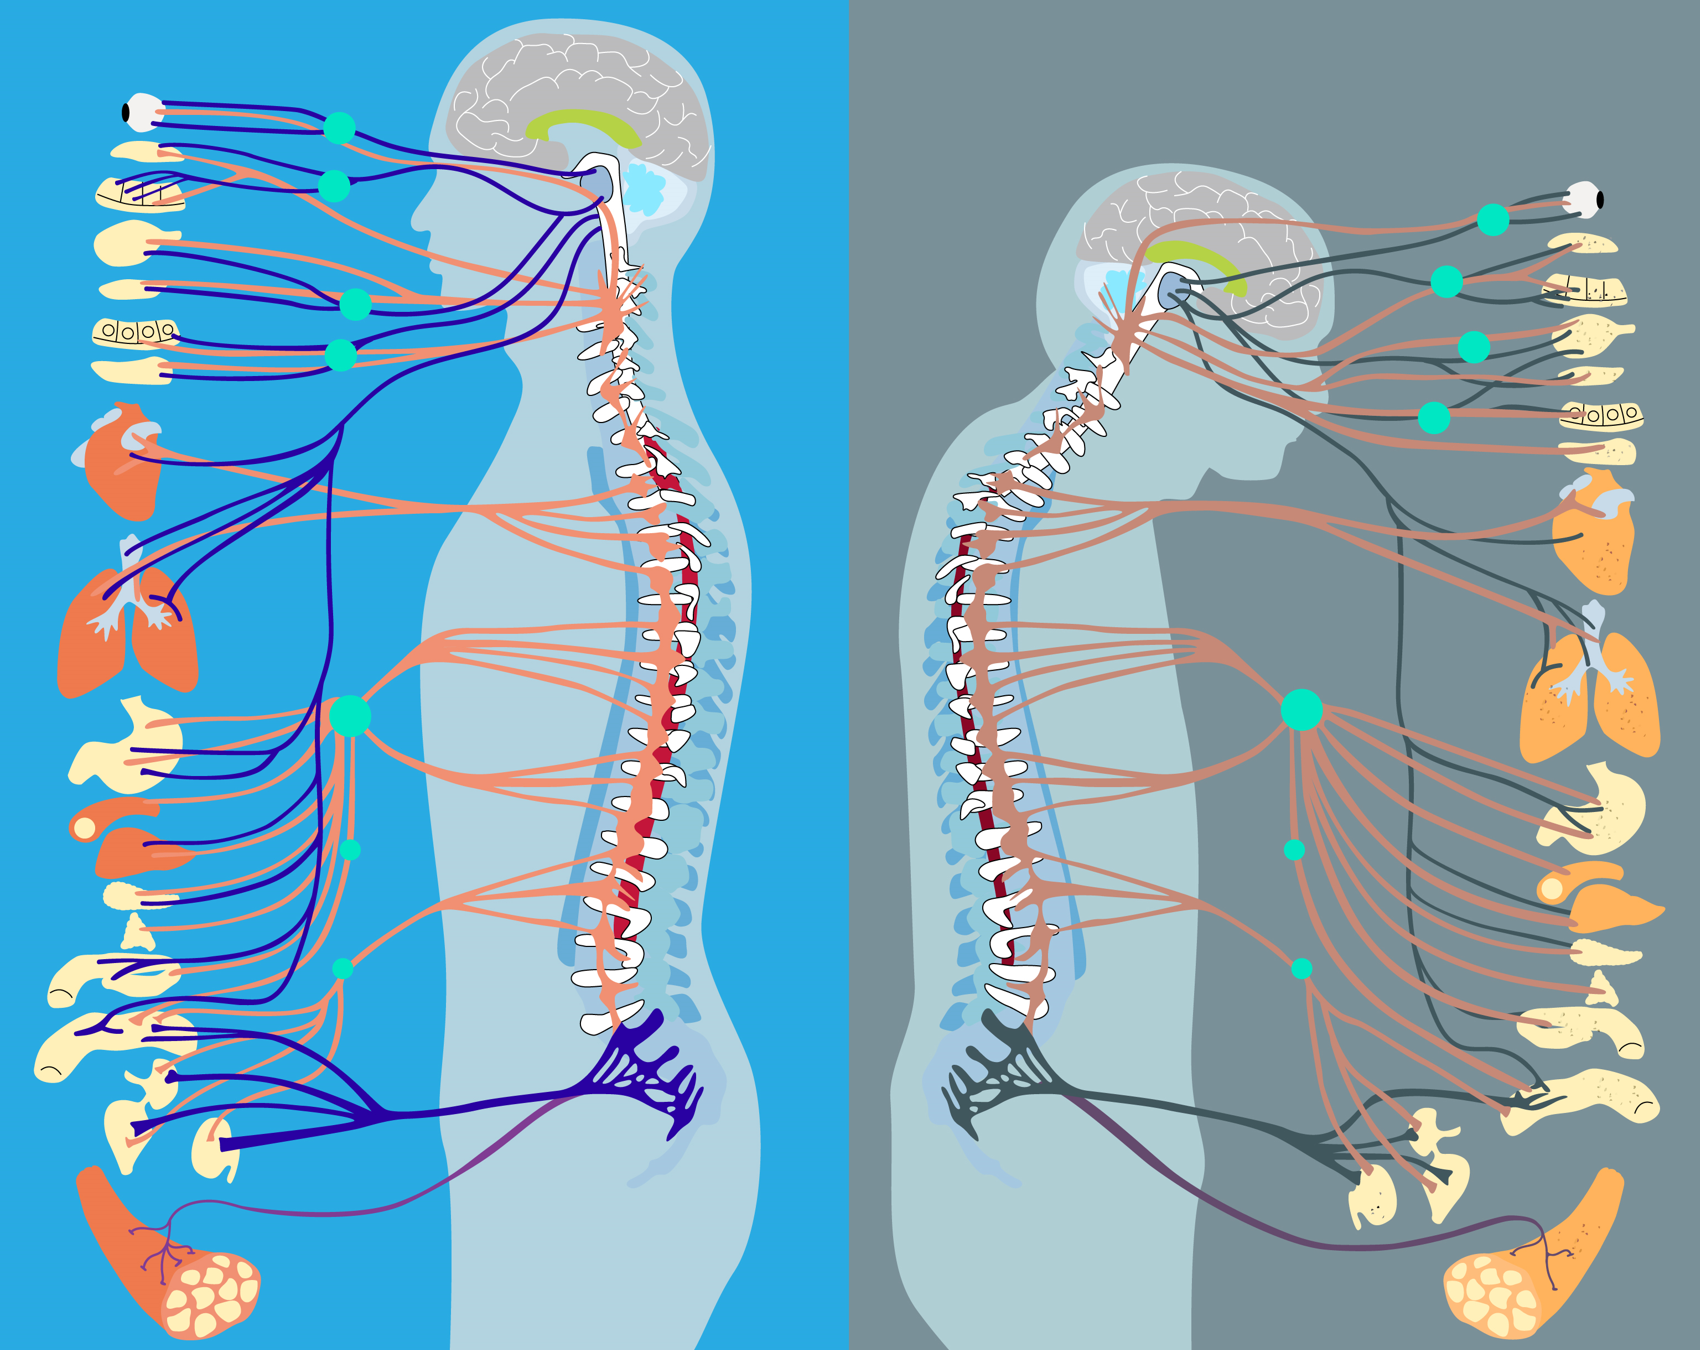

脊髓作为中枢神经系统的重要组成部分,是连接大脑和周围神经的重要桥梁,支配着全身各种运动功能。而这些运动调节功能的主要执行者则是脊髓内一群稀少(仅占脊髓全部细胞约0.3-0.4%)而又关键的细胞——运动神经元(motor neuron)。运动神经元最重要的功能是通过支配全身的骨骼肌实现对机体运动行为的控制。据统计,老年人在60岁以后会发生运动能力的快速下降,65岁以上的老年人平均每年都会因行动不便等原因发生一次以上跌倒事件,20-30%的老年人经历过中度甚至重度摔伤,严重影响了活动能力和生活质量。除了调节肢体运动,运动神经元还能通过植物神经系统协同控制机体的呼吸、心跳、摄食和排泄等一系列基本生命活动。由此可见,脊髓是人体运动及基本脏器自主活动的“指挥部”。脊髓的老化可能导致多器官系统功能障碍,引发行动不便、心律失常、血压失调、胸闷气短等问题,是老年人多种慢病共存的重要因素之一。

图1. 脊髓衰老与多种脏器的退变密切相关